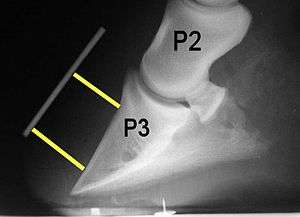

Radiographs

Radiographs are an important part of evaluating the laminitic horse. They not only allow the practitioner to determine the severity of the episode, which does not always correlate with degree of pain,[1] but also to gauge improvement and response to treatment. Several measurements are made to predict severity. Additionally, radiographs also allow the visualization and evaluation of the hoof capsule, and can help detect the presence of a lamellar wedge or seromas.[1] The lateral view provides the majority of the information regarding degree of rotation, sole depth, dorsal hoof wall thickness, and vertical deviation.[1][16] A 65-degree dorsopalmar view is useful in the case of chronic laminitis to evaluate the rim of the coffin bone for pathology.[1]

- Radiographic measurements

Several radiographic measurements, made on the lateral view, allow for objective evaluation of the episode.

- Coronary Extensor Distance (CE): the vertical distance from the level of the proximal coronary band to the extensor process of P3. It is often used to compare progression of the disease over time, rather than as a stand-alone value. A rapidly increasing CE value can indicate distal displacement (sinking) of the coffin bone, while a more gradual increase in CE can occur with foot collapse. Normal values range from 0–30 mm, with most horses >12–15 mm.[1]

- Sole Depth (SD): the distance from the tip of P3 to the ground.

- Digital Breakover (DB): distance from the tip of P3 to the breakover of the hoof (dorsal toe).[1]

- Palmar angle (PA): the angle between a line perpendicular to the ground, and a line at the angle of the palmar surface of P3.

- Horn:Lamellar Distance (HL): the measurement from the most superficial aspect of the dorsal hoof wall to the face of P3. 2 distances are compared: a proximal measurement made just distal to the extensor process of P3, and a distal measurement made toward the tip of P3. These two values should be similar. In cases of rotation, the distal measurement will be higher than the proximal. In cases of distal displacement, both values will increase, but may remain equal. Therefore, it is ideal to have baseline radiographs for horses, especially for those at high-risk for laminitis, to compare to should laminitis ever be suspected. Normal HL values vary by breed and age:[1]